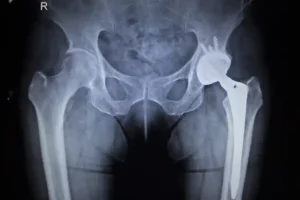

Synovo Hip Implants: FDA Alert About Risks

Urgent Alert: FDA Warnings on Synovo Hip Implants The U.S. Food and Drug Administration (FDA) has issued a critical warning in January of 2024 against the use of Synovo Total Hip Replacement Implants due to significant unauthorized modifications. These changes have raised serious concerns about the safety and efficacy of these medical devices, originally cleared…

FDA Warning on Synovo Hip Implants

Understanding the FDA Warning: The Risks of Synovo Total Hip Replacement Implants The U.S. Food and Drug Administration (FDA) has recently issued a significant warning to healthcare providers and patients regarding the use of Synovo Total Hip Replacement Implants. This advisory comes in light of discoveries that substantial modifications have been made to the system’s…